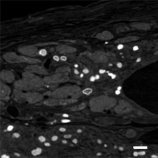

2018/10/30  京都大学,カルフォルニア大学ポイント 心筋細胞にはT管注1や2つ組注2といったナノ構造注3があり、観察には電子顕微鏡注4が必要であるが、 電子顕微鏡画像は倍率が非常に高いため、観察した細胞が移植した心筋細胞かどうか確...